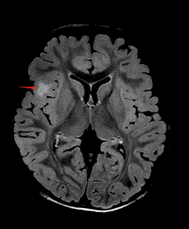

局灶性皮质发育不良(FCD):大脑皮层神经元排列紊乱,形成异常放电网络。

图为2岁男孩,右侧盖区FCD病变,手术切除后癫痫无发作